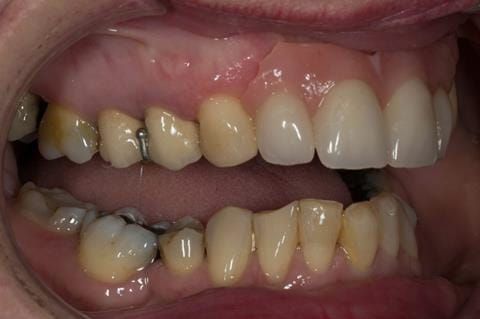

Provision of a maxillary cobalt chromium based partial denture/protective occlusal splint in a heavily restored dentition

- UR2 peri-radicular periodontitis with a peri-radicular area on the root apex. Retrograde amalgam filling from a previous apicectomy. No visible root canal or root canal filling. Large circumferential marginal gap between the crown and tooth. Large post and core present. Very little tooth structure remaining resulting in a fragile tooth with increased potential for fracture.

- UR1 peri-radicular periodontitis with a small peri-radicular area on the root apex with wide blunderbuss apex. Radio-opaque root canal filling present approximately 3 mm short of the radiographic apex. Large circumferential marginal gap between the crown and tooth. Large post and core present. Very little tooth structure remaining resulting in a fragile tooth with increased potential for fracture.

- UL1 peri-radicular periodontitis with a peri-radicular area on the root apex. Retrograde amalgam filling from a previous apicectomy. Visible root canal space with no sign of root canal filling. Large circumferential marginal gap between the crown and tooth. Large post and core present. Very little tooth structure remaining resulting in a fragile tooth with increased potential for fracture.

- UL2 peri-radicular periodontitis with a peri-radicular area on the root apex. No visible root canal or root canal filling. Large circumferential marginal gap between the crown and tooth. Large post and core present. Very little tooth structure remaining resulting in a fragile tooth with increased potential for fracture.

- High smile line showing gum above gingival zeniths of upper front teeth when smiling. Aesthetic failure of the upper four incisors with inflammation of the gingivae and mis-match of the gingival zenith levels.

- Other than the maxillary incisors the remaining dentition was in marginally better condition being moderately to heavily restored. Many will probably require replacement and restoration from time to time mainly from wear and tear owing to occlusal forces.

Following consultation and second discussion appointment the patient chose to have option 3 namely, a maxillary cobalt chromium based partial denture/protective occlusal splint. The clinical situation and treatment process is shown in detail below with photographs. The patient was successfully rehabilitated with this and her quality of life considerably improved. The clinical work was provided by Finlay and the technical work by Rowan.